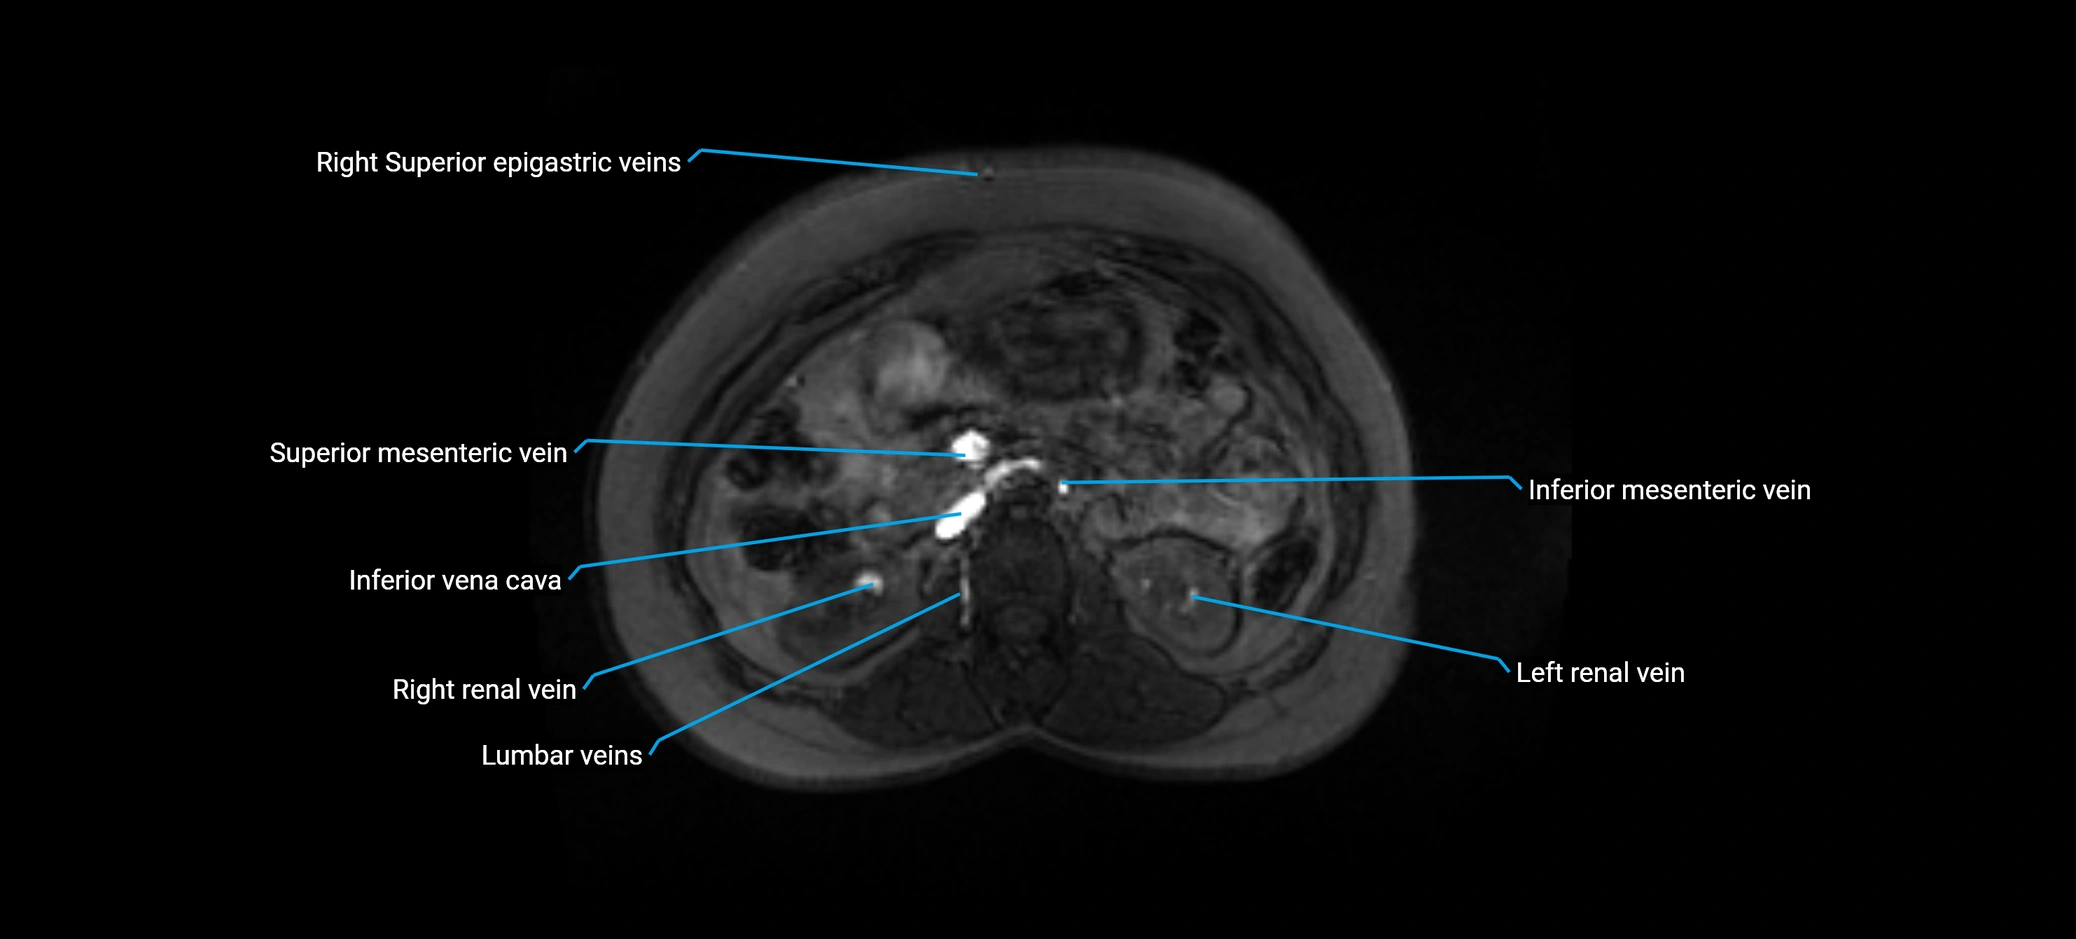

MRI image

image